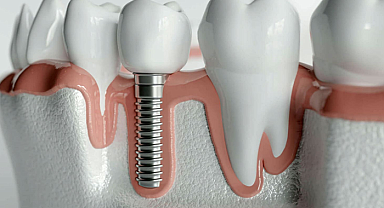

İmplant tedavisinde bu ayrıntılara dikkat edin!